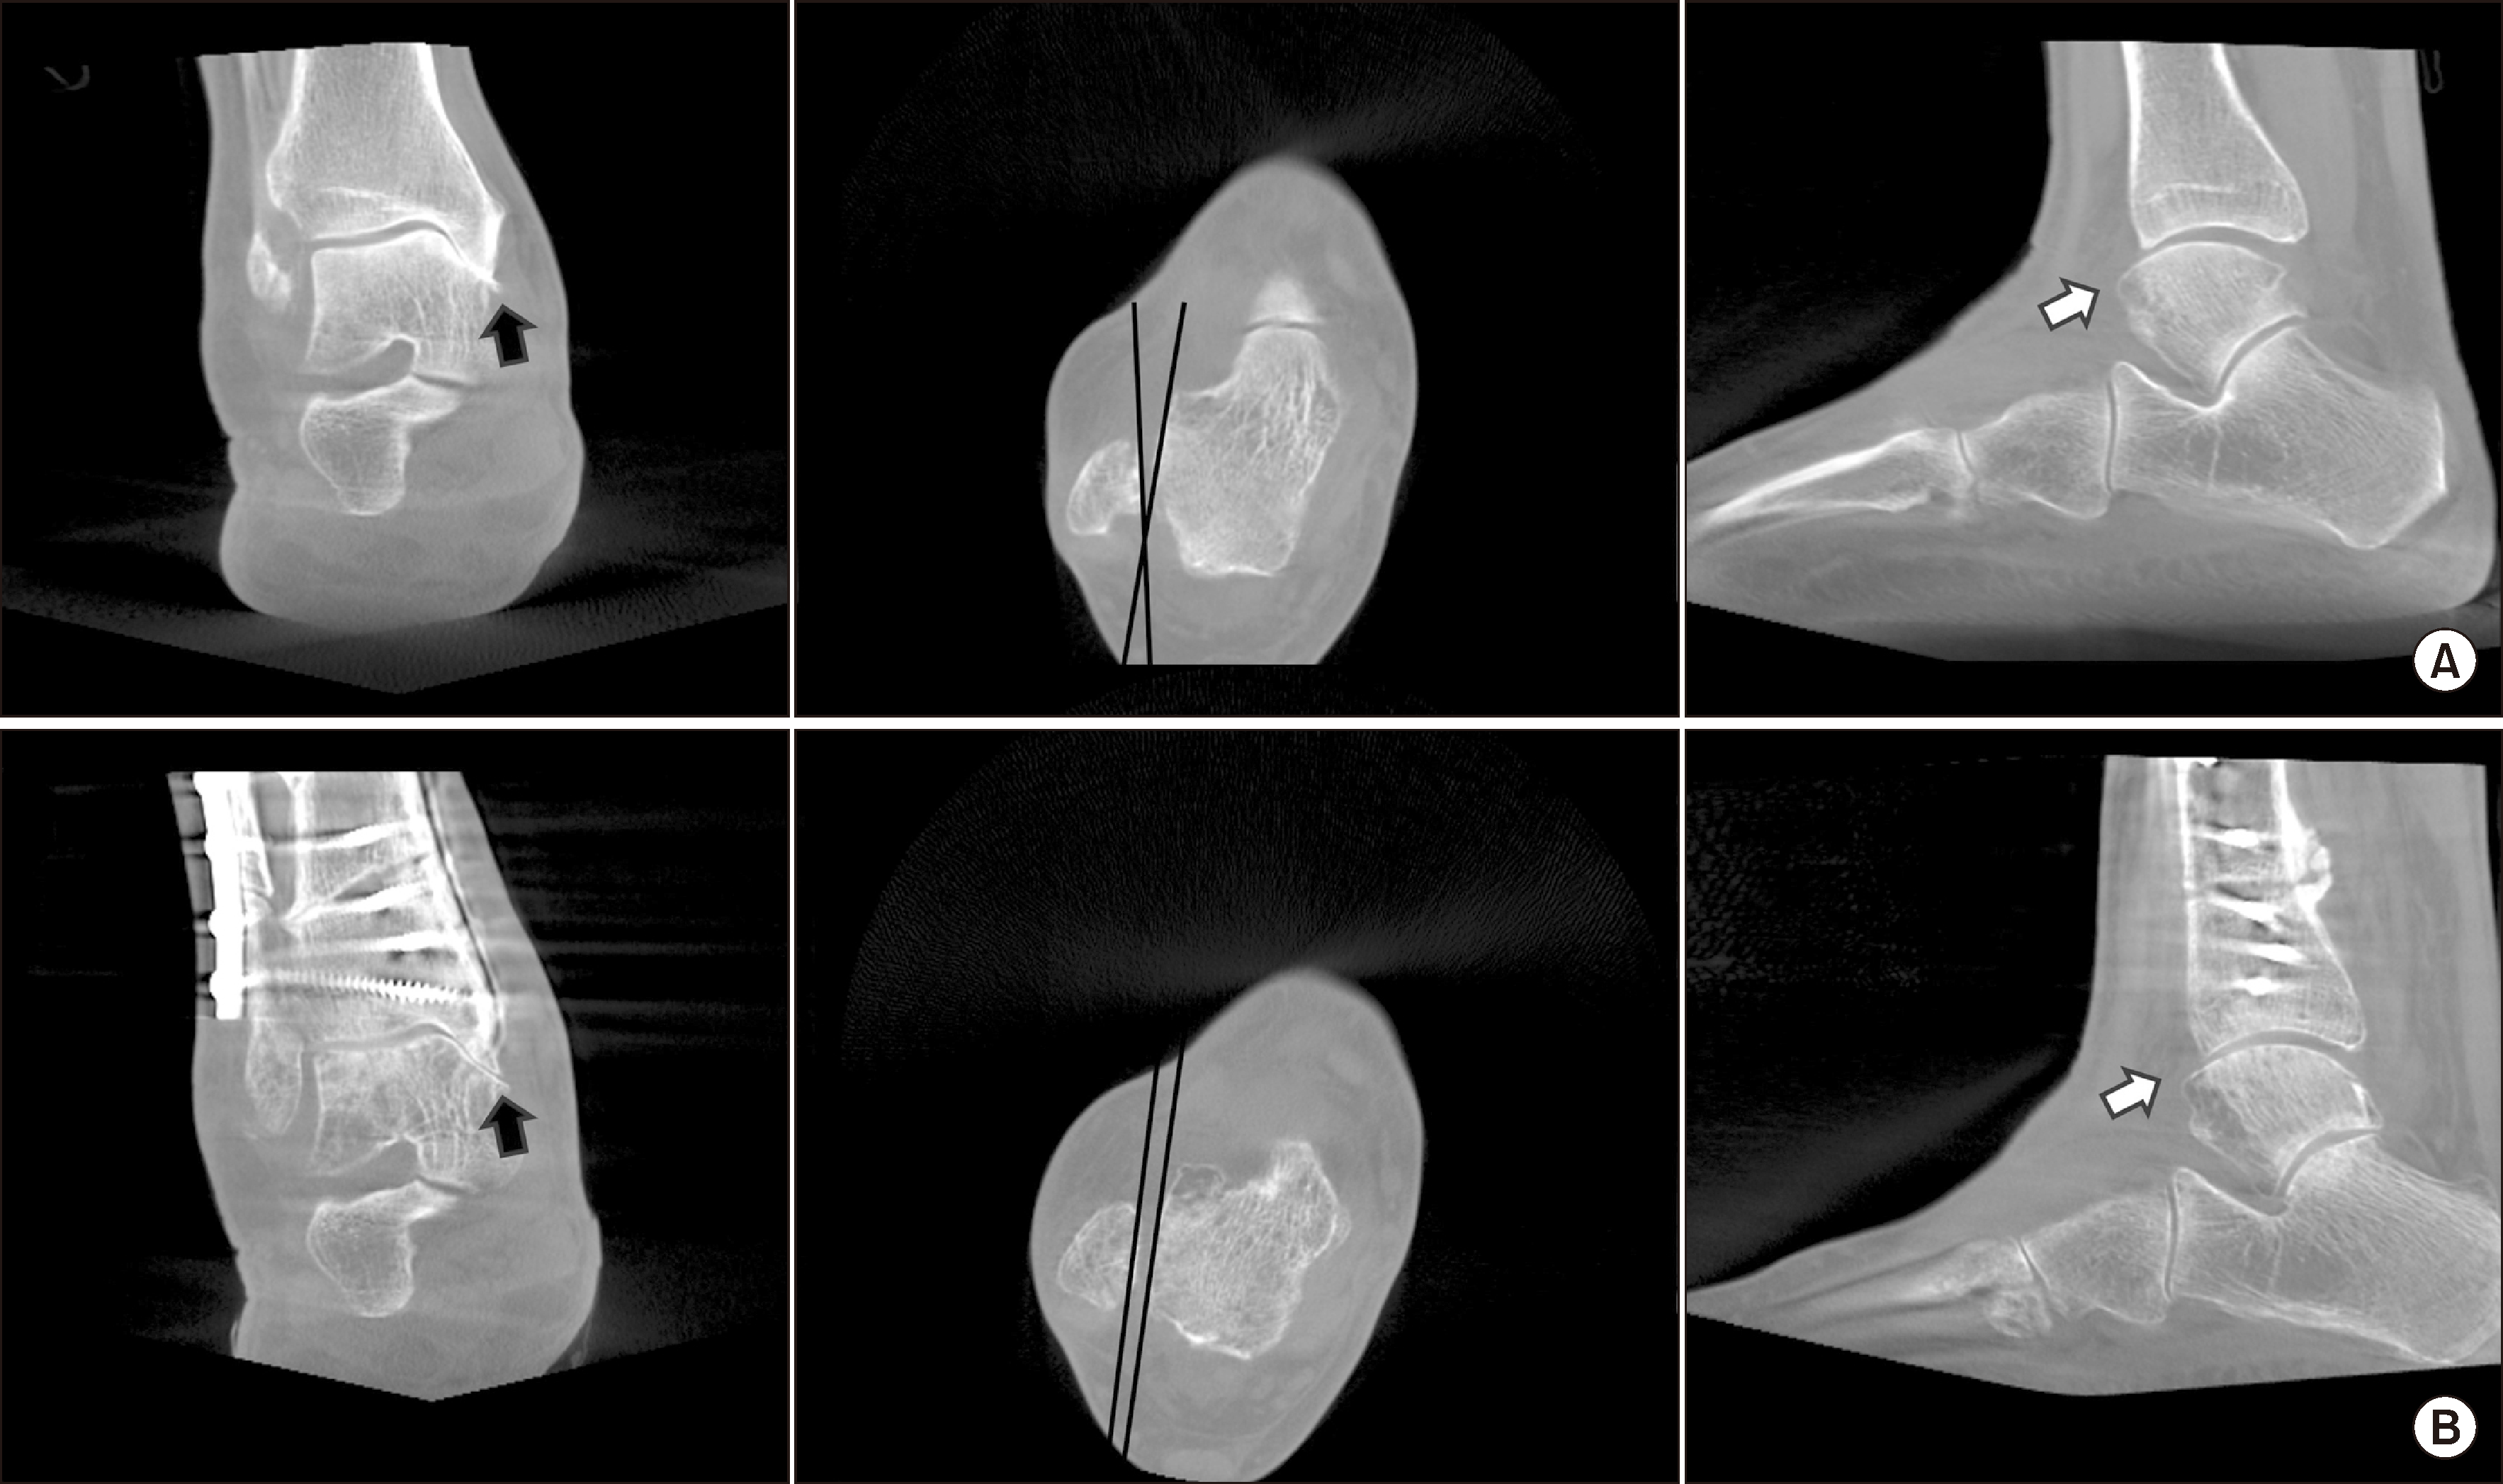

한편, 발목 관절염에서 후족부 정렬(hindfoot alignment)과 거골하 관절의 보상 기전에 대한 진단은 발목 관절염에 대한 치료 계획을 수립하는 데 중요한 요소에 해당된다. 단순 방사선 사진을 이용한 후족부 정렬 측정은 촬영 시 방사선 투사 각도의 영향을 크게 받기 때문에, WBCT를 이용하면 보다 정확한 평가가 가능하다. Krähenbühl 등17)은 초기 연구에서 관상면 WBCT 영상을 이용하여, 내반 발목 관절염에서는 거골하 관절의 내반 정렬, 외반 발목 관절염에서는 거골하 관절의 외반 정렬을 보인다고 보고하였다가, 이후 확대된 샘플 분석을 통해 내반 발목 관절염에서는 거골하 관절이 외반 정렬되는 보상 작용을 하는 것으로 보고하였다.18) Kang 등19)은 진행된 내반 발목 관절염 환자를 대상으로 거골하 관절의 보상 작용 유무에 따라 구분하여 비교 분석을 진행하였는데, 경거골 경사각이 9.5° 이상 증가한 경우에는 뒤꿈치의 보상 기전이 현저히 감소한다는 점을 보고하였다(Fig. 6).

Figure 6

(A) Arthritis showing a difference in the talar tilt angle on standing radiographs of both sides. (B) The compensation of the subtalar joint on weight-bearing computed tomography is observed on the right side with a smaller talar tilt angle, but is not seen on the left side with a larger talar tilt angle.